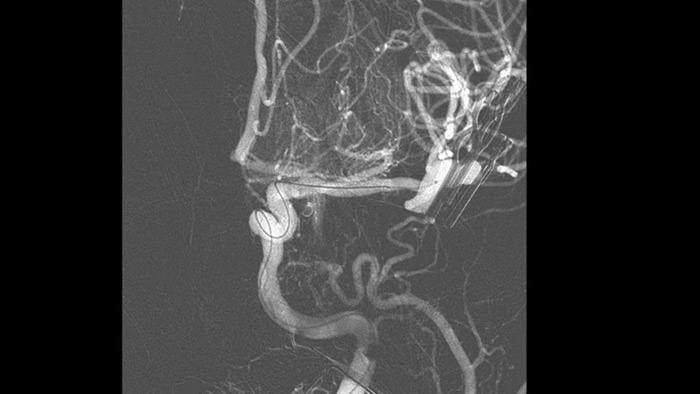

SmartCT Vaso IV

Dank der periprozeduralen Darstellung von Aspekten distaler Gefäße bei ischämischen Schlaganfällen ermöglicht SmartCT Vaso den Blick hinter das Gerinnsel. SmartCT Vaso ist eine Erfassungstechnik, die auf einem Cone-Beam-CT-Scan in Kombination mit einer intraarteriellen Kontrastmittelinjektion basiert. Durch retrograde Füllung werden die Gefäßstrukturen vor und hinter dem Gerinnsel sichtbar. Die SmartCT Vaso 3D Roadmap kann zur Darstellung von Instrumenten zur Entfernung von Gerinnseln verwendet werden.